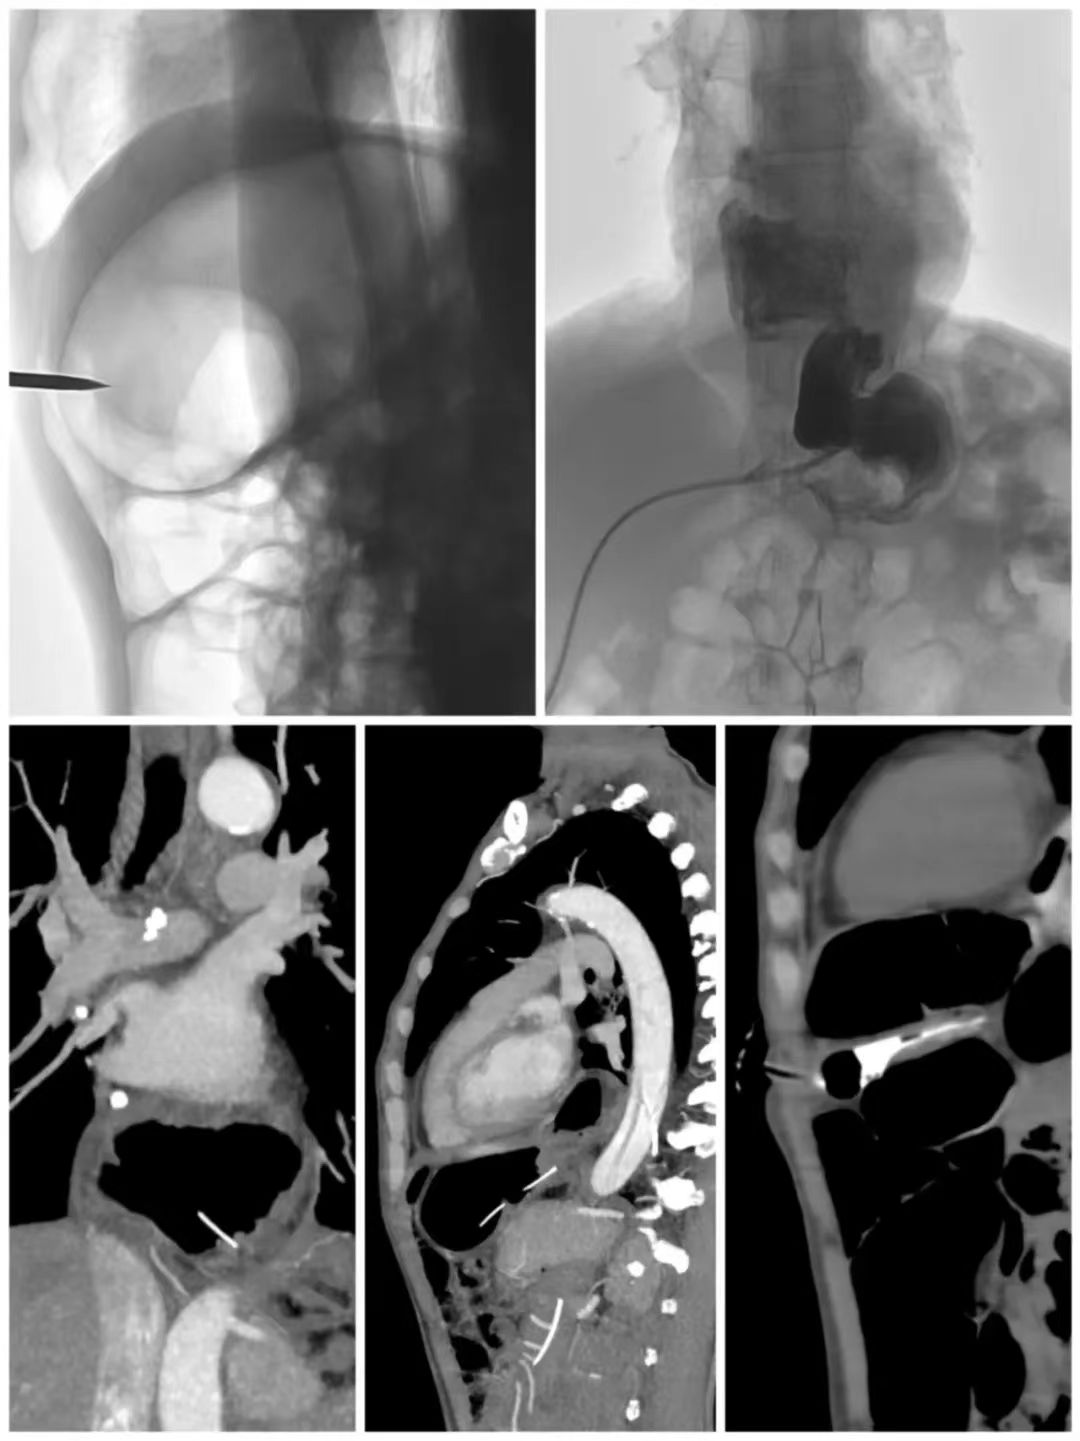

面对这块“硬骨头”,昆明同仁医院肿瘤科专家团队没有退缩。“患者把希望寄托给我们,我们就必须想方设法,不能因为风险高,就剥夺他改善生活质量的权利。”吴伦医生说。经过多次讨论,团队最终制定了一套详细而周密的手术方案:利用医院先进的数字减影血管造影(DSA)和锥形束CT(CBCT)设备,为手术打造“双重保险”。

术中,在DSA影像的引导下,吴伦医生将造影导管置入胃腔并注入空气,使胃壁与腹壁贴合,为穿刺创造条件。随后,团队凭借CBCT生成的三维图像,精准掌握食管裂孔疝与间位结肠的解剖关系,凭借实时透视功能,穿刺针精准避开危险区域,沿安全路径一次成功穿入胃内,整个过程一气呵成。